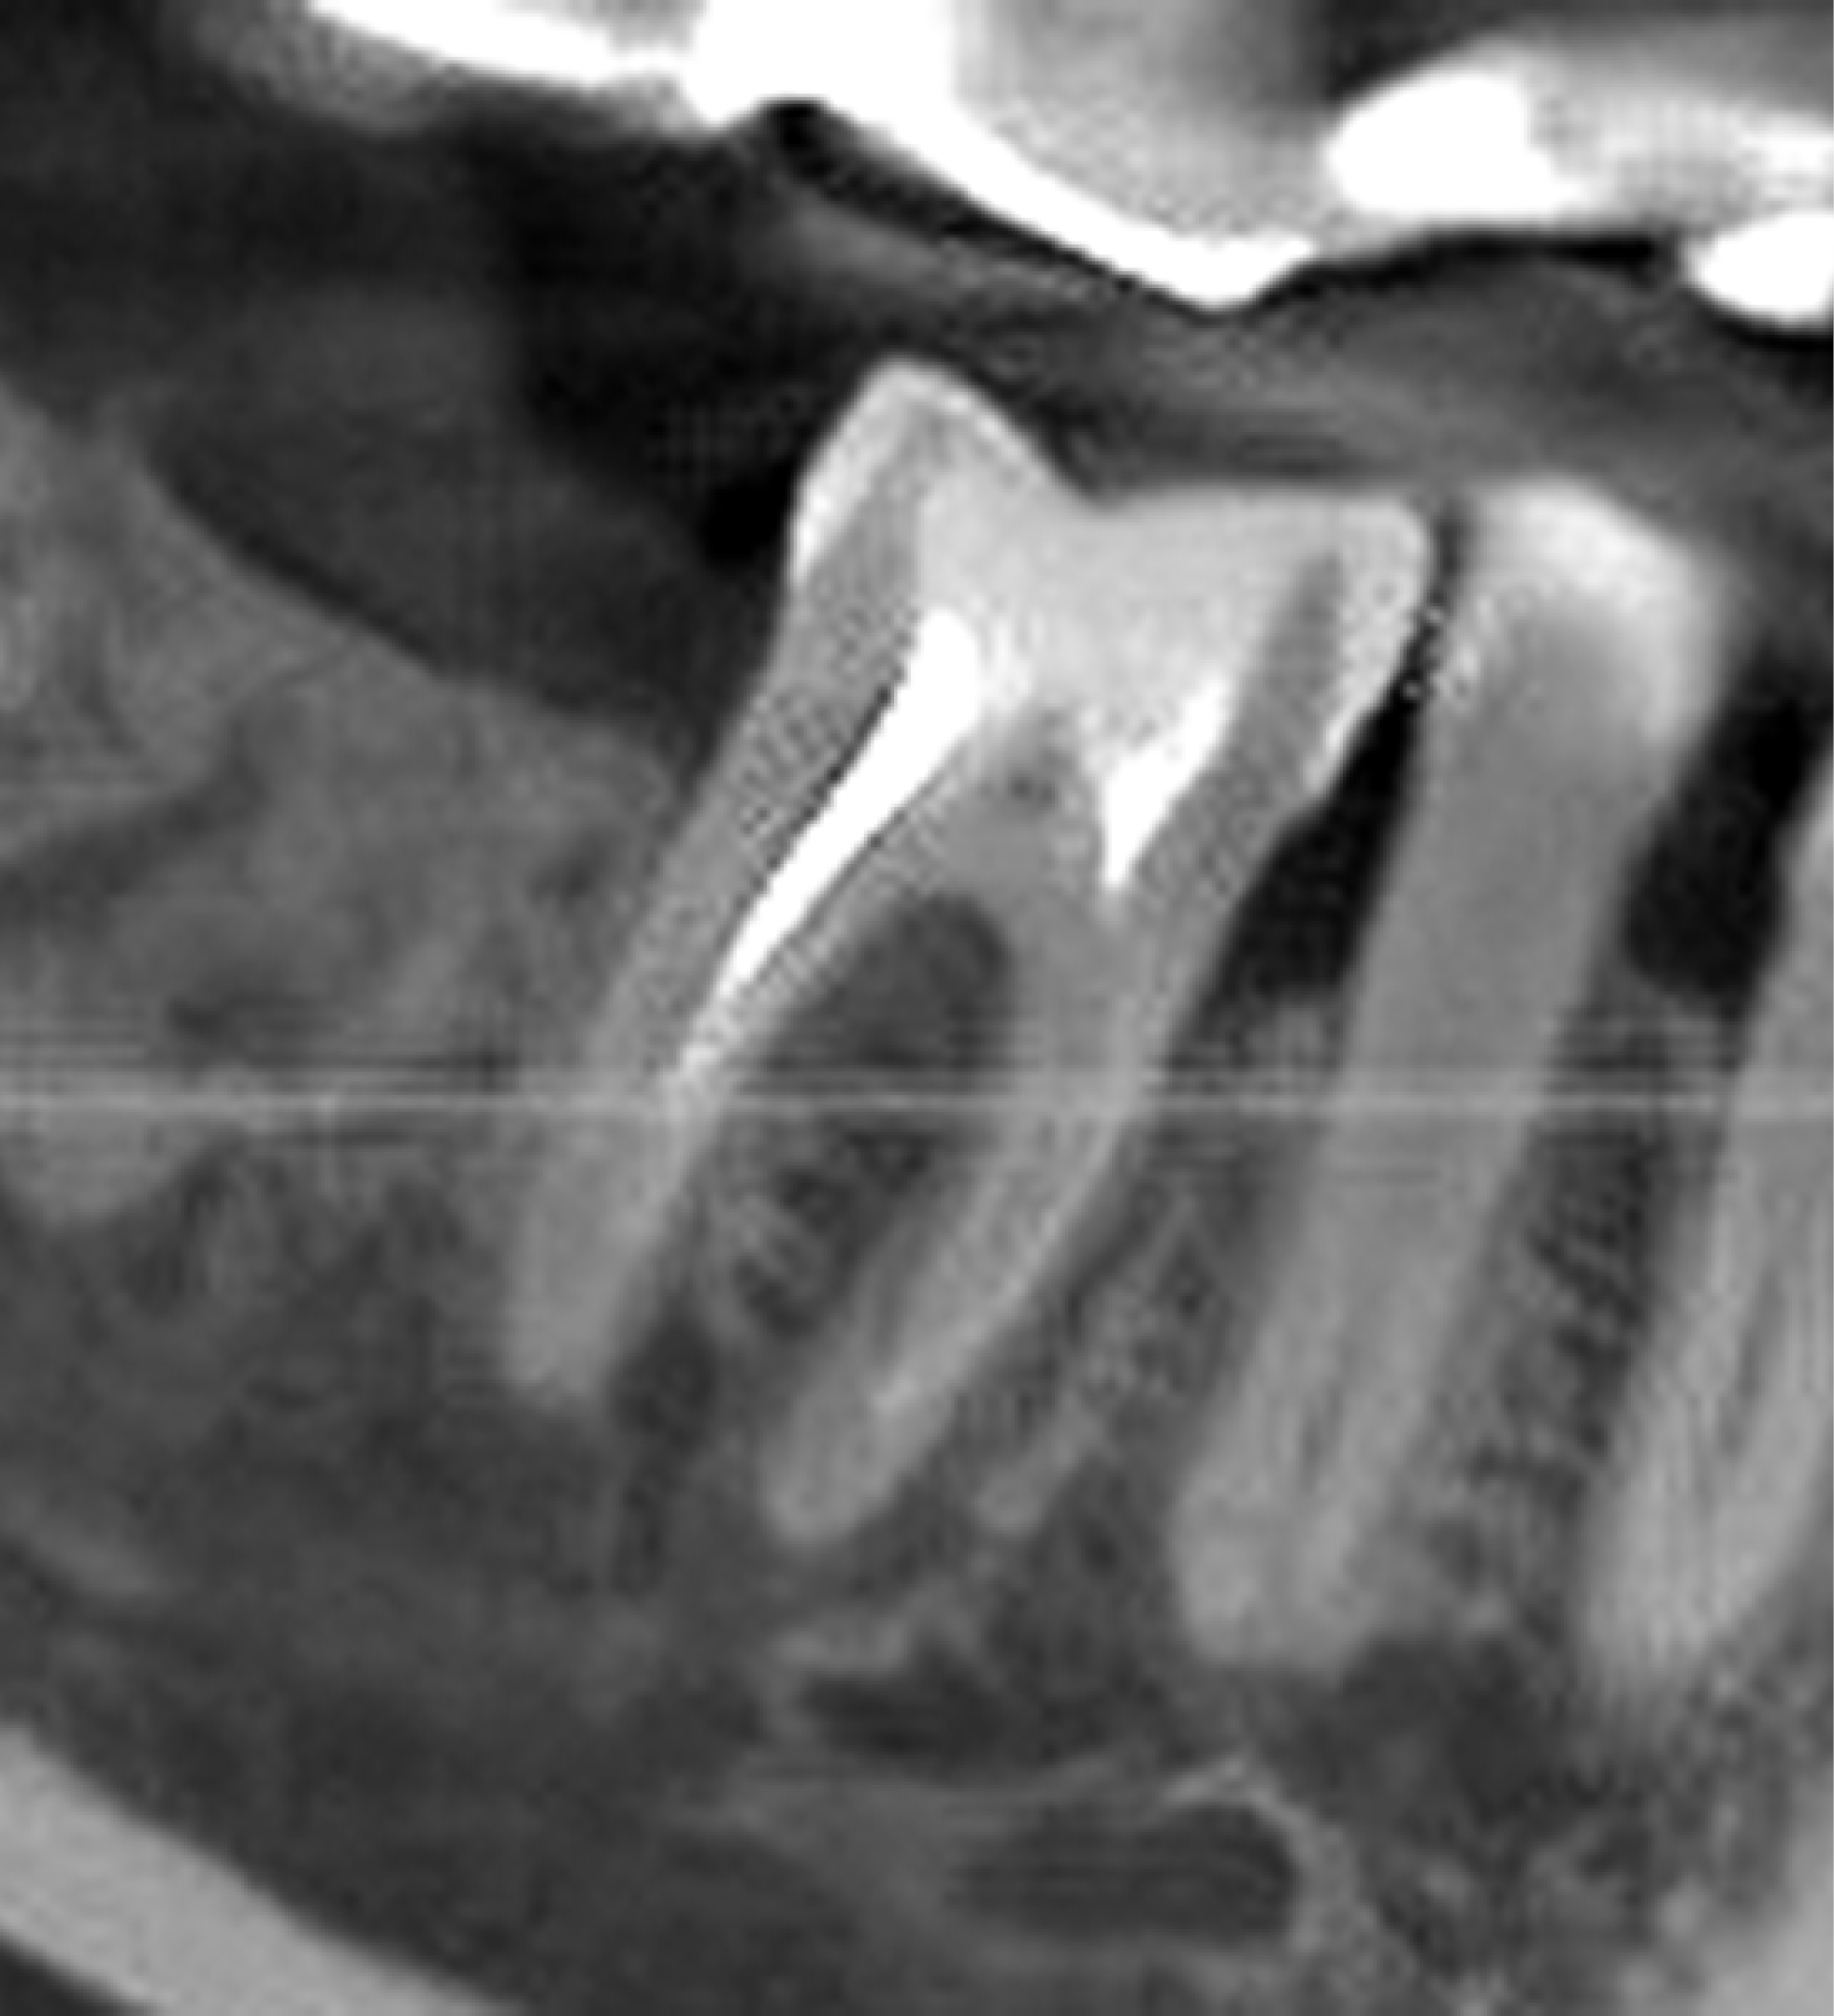

В 1-й группе (рис. 1) использовали комбинацию материалов «Остеоматрикс», «Биоимплант ГАП», «Биоматрикс» («Конектбиофарм», Россия). Исследовали заполнение костного дефекта спустя 5 мес с помощью конусно-лучевой компьютерной томографии (КЛКТ). Был отмечен хороший показатель плотности кости. Гистологическое исследование выполняли путём забора костной ткани перед операцией дентальной имплантации в области отсутствующих зубов спустя 5 мес после удаления, с консервацией лунки костнопластическими материалами.

Рис. 1. Фронтальная плоскость области костной пластики материалами «Остеоматрикс», «Биоимплант ГАП», «Биоматрикс» (мембрана коллагеновая) спустя 5 мес. Конусно-лучевая компьютерная томография